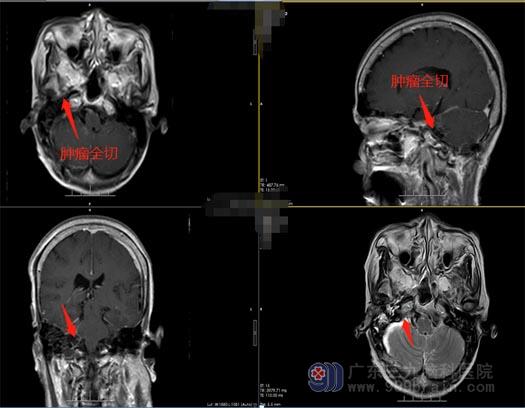

李婆婆的颅内占位效应明显,有颅神经损害的症状,神经外五科治疗团队建议手术治疗,李婆婆和家人也非常赞同治疗方案。经过周密的准备,治疗团队为李婆婆施行了“右侧桥小脑角区神经鞘瘤切除术”,术中见肿瘤位于右侧桥小脑角,黄白色,质中,予显微镜下电凝分块切除,右侧前庭神经位于肿瘤下方、面神经位于肿瘤上方,经分离面神经保留完整,三叉神经、舌咽神经受肿瘤压迫明显,经细心分离完整保留,肿瘤于显微镜下全切,右侧内听道肿瘤给予反复电凝烧灼,术腔止血彻底。

术后,李婆婆恢复很好,无饮水呛咳、面瘫等症状,耳鸣症状也消失了。